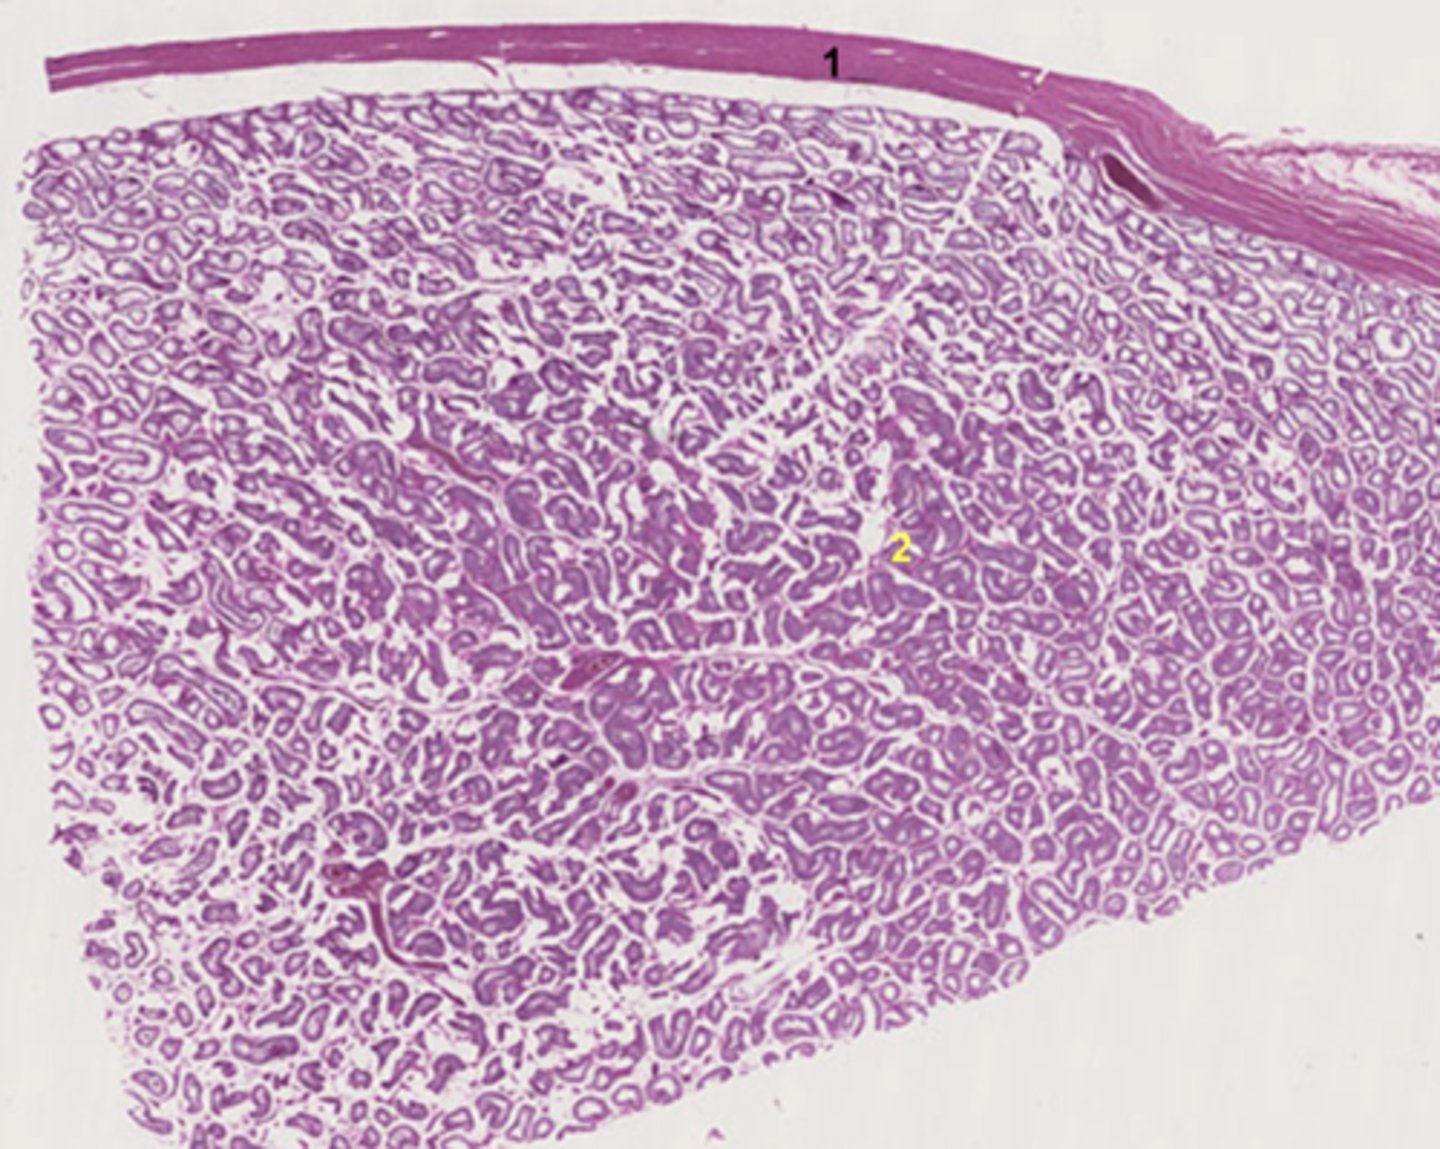

Tunica albuginea

What is 1?

Testis

What is 2?

Seminiferous tubule